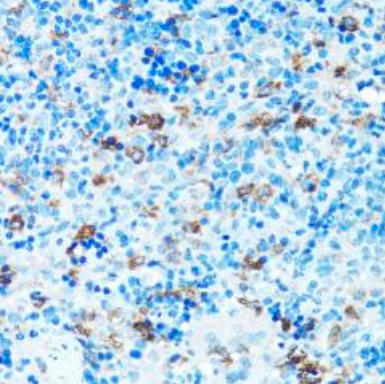

The Medikbio Anti-FGFR2 Antibody (1–100) – Catalog No. MDB23658 is a high-quality rabbit polyclonal antibody developed to detect Fibroblast Growth Factor Receptor 2 (FGFR2), a critical receptor tyrosine kinase involved in cell proliferation, differentiation, angiogenesis, and cancer progression. Designed for optimal performance in Immunohistochemistry (IHC), this antibody provides strong, clear staining with minimal background, enabling precise FGFR2 localization in both human and animal tissues.

Produced using a synthetic peptide corresponding to amino acids 1–100 of human FGFR2, the antibody demonstrates high specificity and robust reactivity with Human, Mouse, and Rat samples—making it ideal for studies involving oncology, developmental biology, and molecular signaling. Affinity purification ensures superior binding performance and reliable IHC detection, even in complex tissue environments.

FGFR2 dysregulation is widely implicated in diseases such as breast cancer, gastric cancer, endometrial cancer, craniosynostosis syndromes, skeletal abnormalities, and developmental disorders. This antibody provides researchers with a powerful tool for mapping FGFR2 expression patterns and investigating receptor-mediated pathways across various biological and pathological models.